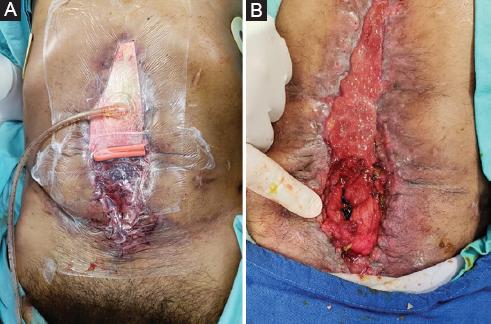

Se decide una tercera intervención en el hospital de tercer nivel, el 9 de abril, desmantelando la anastomosis previa, la cual presentaba dehiscencia de más del 70%. Se decide hemicolectomía derecha con la finalidad de prevenir fugas debido a la pobre irrigación del remanente de ciego y de colon ascendente. Se realiza anastomosis transverso-yeyuno. No es posible separar el yeyuno adherido al colon sigmoides (Fig. 2). Al cuarto día se produce fuga de la anastomosis por acodamiento en el colon sigmoides y aumento de la presión (Fig. 3). Para limitar la contaminación de la cavidad, se coloca un sistema de cierre asistido por presión (VAC) (Fig. 4), lo cual permite el cierre de la línea media de la herida en cuatro sesiones de VAC, dejando únicamente la dehiscencia de anastomosis como una fístula enteroatmosférica aislada. Debido a la condición del paciente (desnutrición, sepsis, desequilibrio hidroelectrolítico, abdomen hostil) no son posibles más cirugías, por alto riesgo de perforación y desvascularización. El aislamiento de la fístula ayudó a mejorar el estado hemodinámico y el control de la sepsis; sin embargo, las pérdidas entéricas eran elevadas, lo cual perpetuaba el desequilibrio hidroelectrolítico, la desnutrición y la malabsorción11-14.

En el contexto del paciente con fístula enterocutánea y síndrome de intestino corto se propone la colocación de una endoprótesis recubierta de 36 × 100 mm (nitinol) para restituir el tránsito intestinal desde el asa distal (yeyuno) a proximal (colon transverso), permitiendo el control de la fístula, la granulación desde los bordes intestinales y el cierre definitivo. La intervención se realizó el día 16 de mayo, colocando la endoprótesis a través de la línea media invaginando los dos segmentos del stent y fijándolo con puntos de sutura no absorbible. Mediante colonoscopia transoperatoria se colocó un segundo stent en el sigmoides para reducir la presión intraluminal y prevenir fugas9,10 (Fig. 5). Después de la colocación de los stents disminuyó el gasto de la fístula, de 1500 a 200 ml, en un periodo de 5 días. Se inició la alimentación enteral, coincidiendo con un incremento del gasto, el cual se estabilizó hasta 300 ml. El paciente continuó con nutrición parenteral total a razón de 30 kcal/kg al día (Fig. 6). Al noveno día posquirúrgico se decide el alta, sin evidencia de sepsis ni de desequilibrio hidroelectrolítico, y con control de la fístula.

Se realizó seguimiento por consulta externa con el equipo multidisciplinario de manera mensual, evaluando el estado nutricional y la herida quirúrgica, que se encontraba cerrada en un 90% a los 6 meses de seguimiento, sin necesidad de nutrición parenteral total, solo suplementación multivitamínica y dieta sin oxalatos, y el gasto a través de la herida era de 50-150 ml (Fig. 7). El paciente se reincorporó de manera parcial a sus actividades diarias y se valía por sí mismo.

Figura 7 Fístula en proceso de cierre por segunda intención. Se observa el stent en el tercio medio.